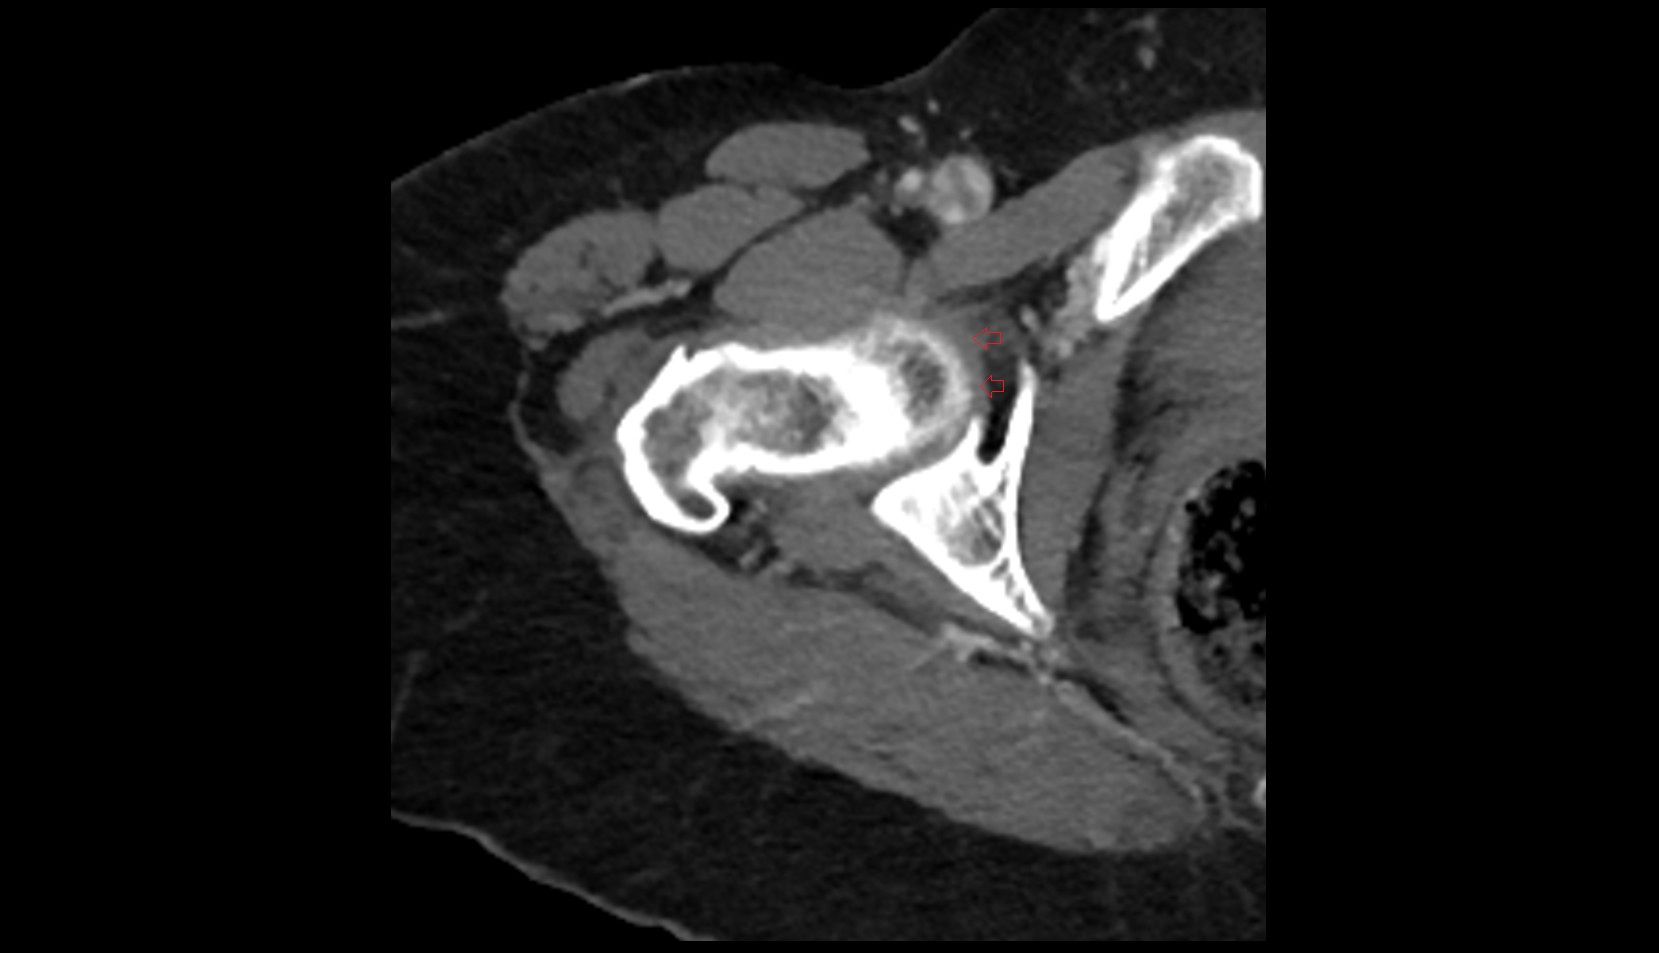

- Hip joint

- Head of femur

- Acetabulum